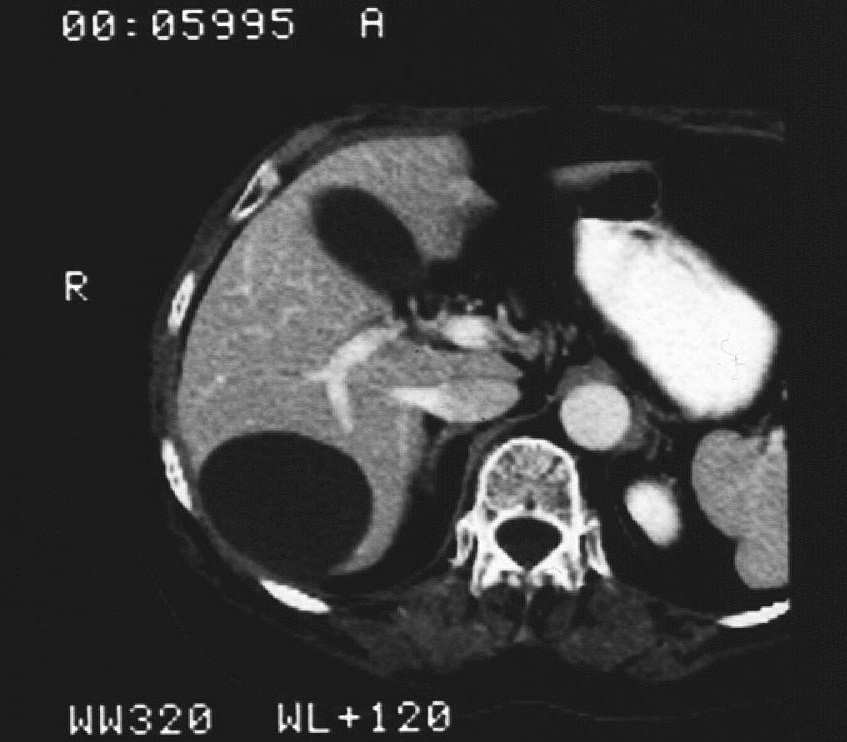

19.2.2.2. CT guided biopsy

Ideal method if the lesion is located either in the chest (figure 5.), mediastinum, retroperitoneum (figure 6.) or the pelvis.

Image

Figure 6. – CT guided pancreatic biopsy